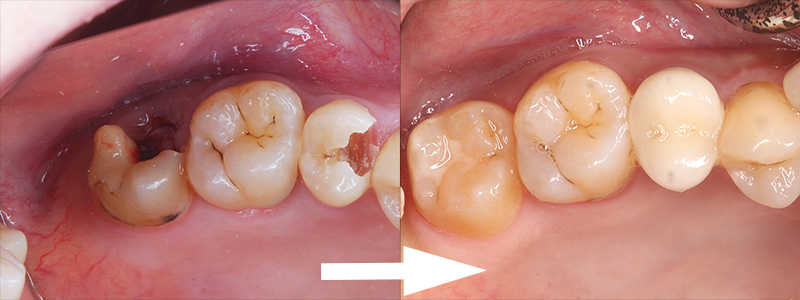

世代が上がれば後方の90度変位した埋伏智歯の移植利用を考えるが歯髄失活は免れないため、困難な矯正であるが萌出間もない大臼歯として今後を託せる生活歯のまま保存する。 矯正用のアンカースクリューと各種装置を智歯に接着させ、移動の各段階で交換しながら抜歯した第二大臼歯部に誘導する。 第一大臼歯は保存治療後ジルコニアセラミック冠で歯冠修復し約7年経過。 治療期間は 2017/12~2019/03

前方大臼歯抜歯時に矯正用アンカーを歯槽骨にねじ込み、引張用のアタッチメントを智歯歯冠に接着

矯正力のかけ方は智歯の萌出状態によって変更